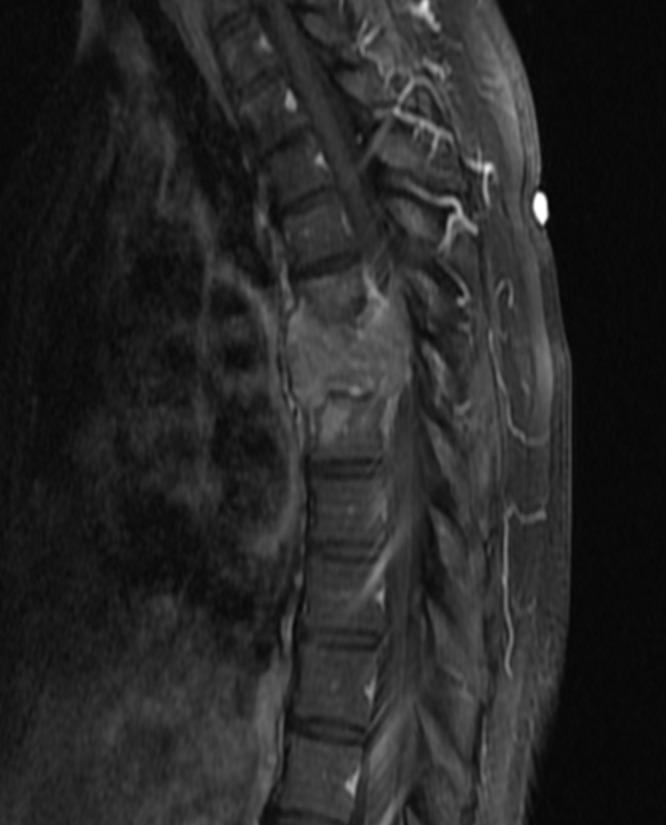

Thoracic Spinal Cord Compression Secondary to Metastatic Papillary Thyroid Carcinoma: An Unusual Oncological Phenomenon.

Cureus. 2022 Apr 17;14(4):e24206. doi: 10.7759/cureus.24206. eCollection 2022 Apr.

Unusual metastasis of papillary thyroid carcinoma to the spine: A case report.

Radiol Case Rep. 2023 Sep 7;18(11):4110-4114. doi: 10.1016/j.radcr.2023.08.078. eCollection 2023 Nov.